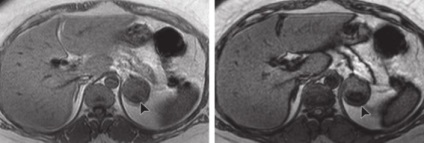

MR modificări de schimbare chimică utilizează frecvențe diferite precesional de protoni în apă față de protoni grăsime din cadrul aceluiași voxel și creează în fază și în afara faze de imagine în care un semnal de protoni sunt însumate sau scăzute unul de altul. Această secvență evaluează grăsime intracitoplasmatică găsite în cele mai multe adenoamelor. Cele mai multe adenoame arată o scădere a intensității semnalului în imagini de fază distincte.

MR. T1VI hiperplazie sau adenom.

hemoragie suprarenală.

CT. Periph. câștig. 50-90 HU, scade treptat. Calcifiere poate fi singurul simptom rezidual.